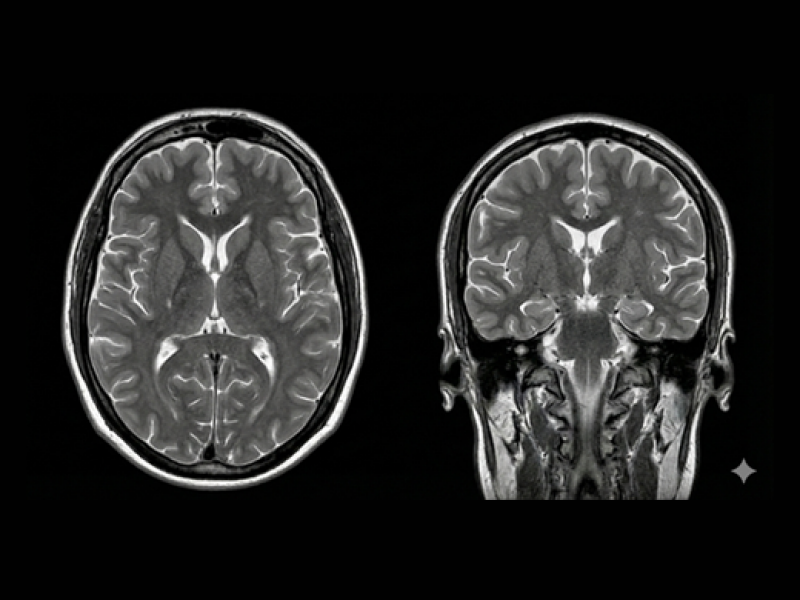

뇌에 혈액을 공급하는 혈관이 막히거나 터져서 뇌손상이 오고 그에 따른 신체 장애가 나타나는 뇌질환을 말합니다.